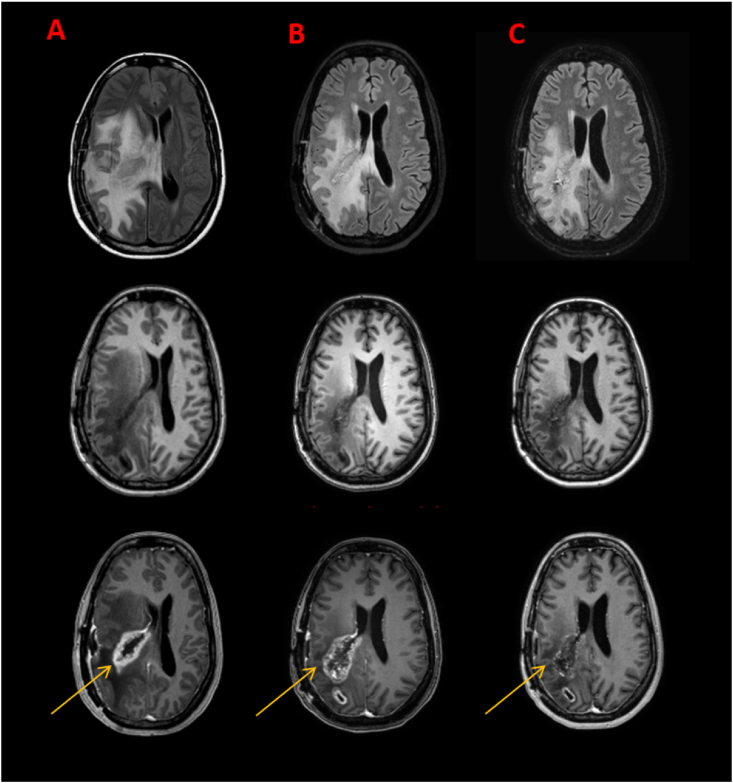

Figure 2.

Case of pseudoprogression in a GBM patient. Sequences: T2/FLAIRw, T1w, T1w Gd-enhanced. (A–C) MRI performed at the beginning of the therapy as well as 3 month and 4,5 month after the therapy start. FLAIR signal and T1 Gd-enhanced (arrows) signal temporarily increases during therapy.